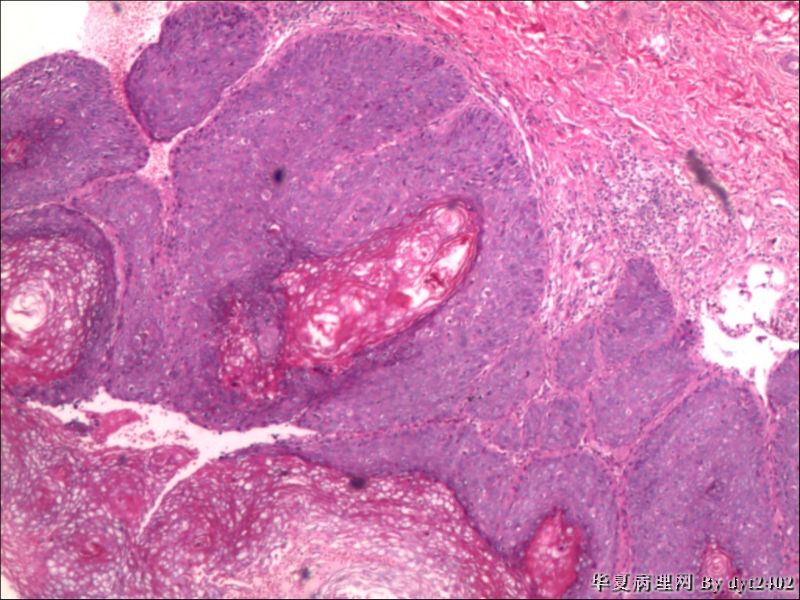

这样的外阴病变 发个原位癌是否合适?

• 这样的外阴病变 发个原位癌是否合适?图4

图4

原位癌够了,不排除其他地方有浸润。

似乎有浸润了

VIN III,做个银染或者标个免疫组化看一下基底膜是否完整。

看上去好像还完整 只是经常看见图5 那样结构的就觉得可能还有更重病变

VIN III